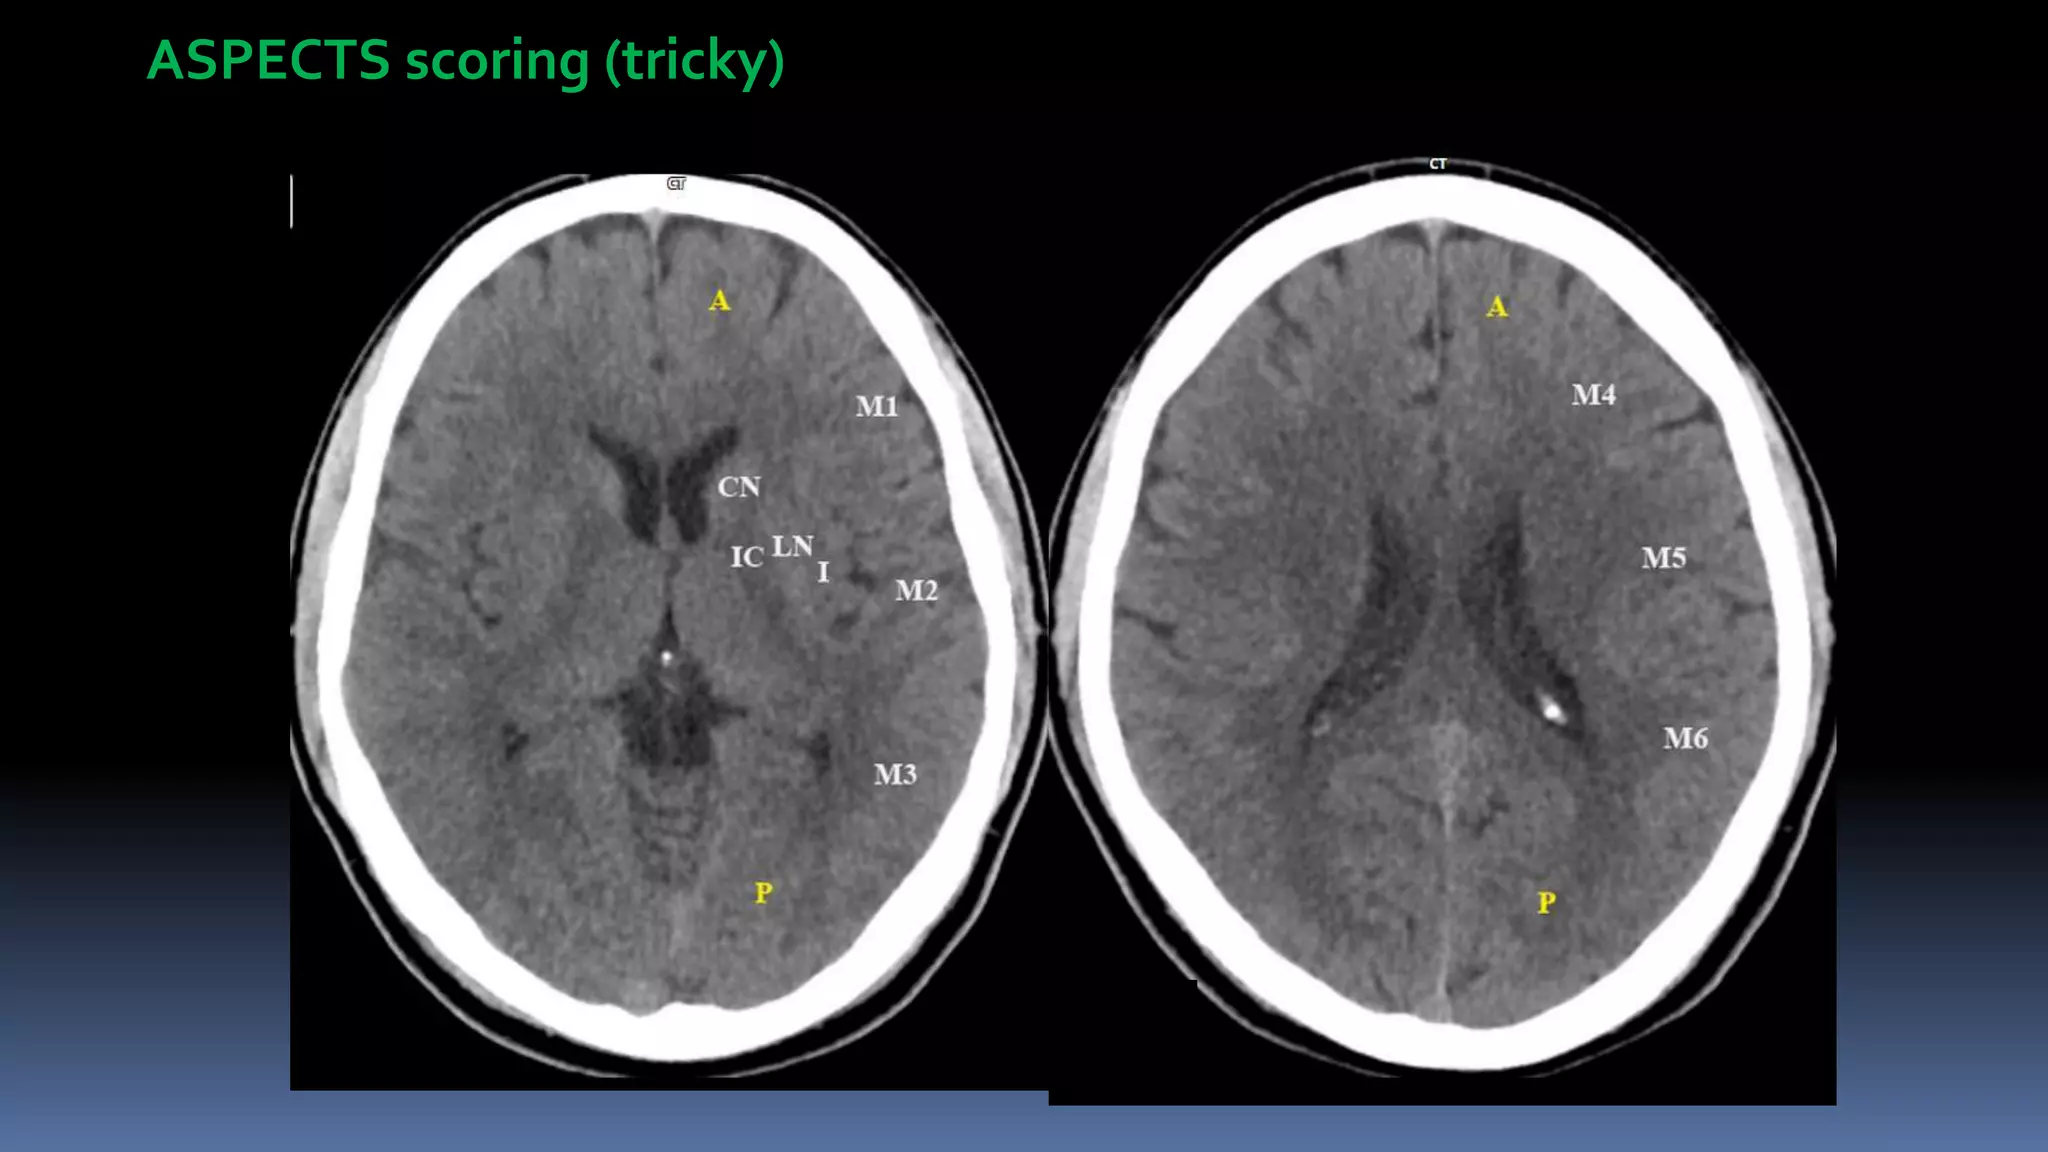

ASPECTS scoring (tricky)

 ASPECTS of ≥ 6

 NCCT (ASPECTS)- NIHSS